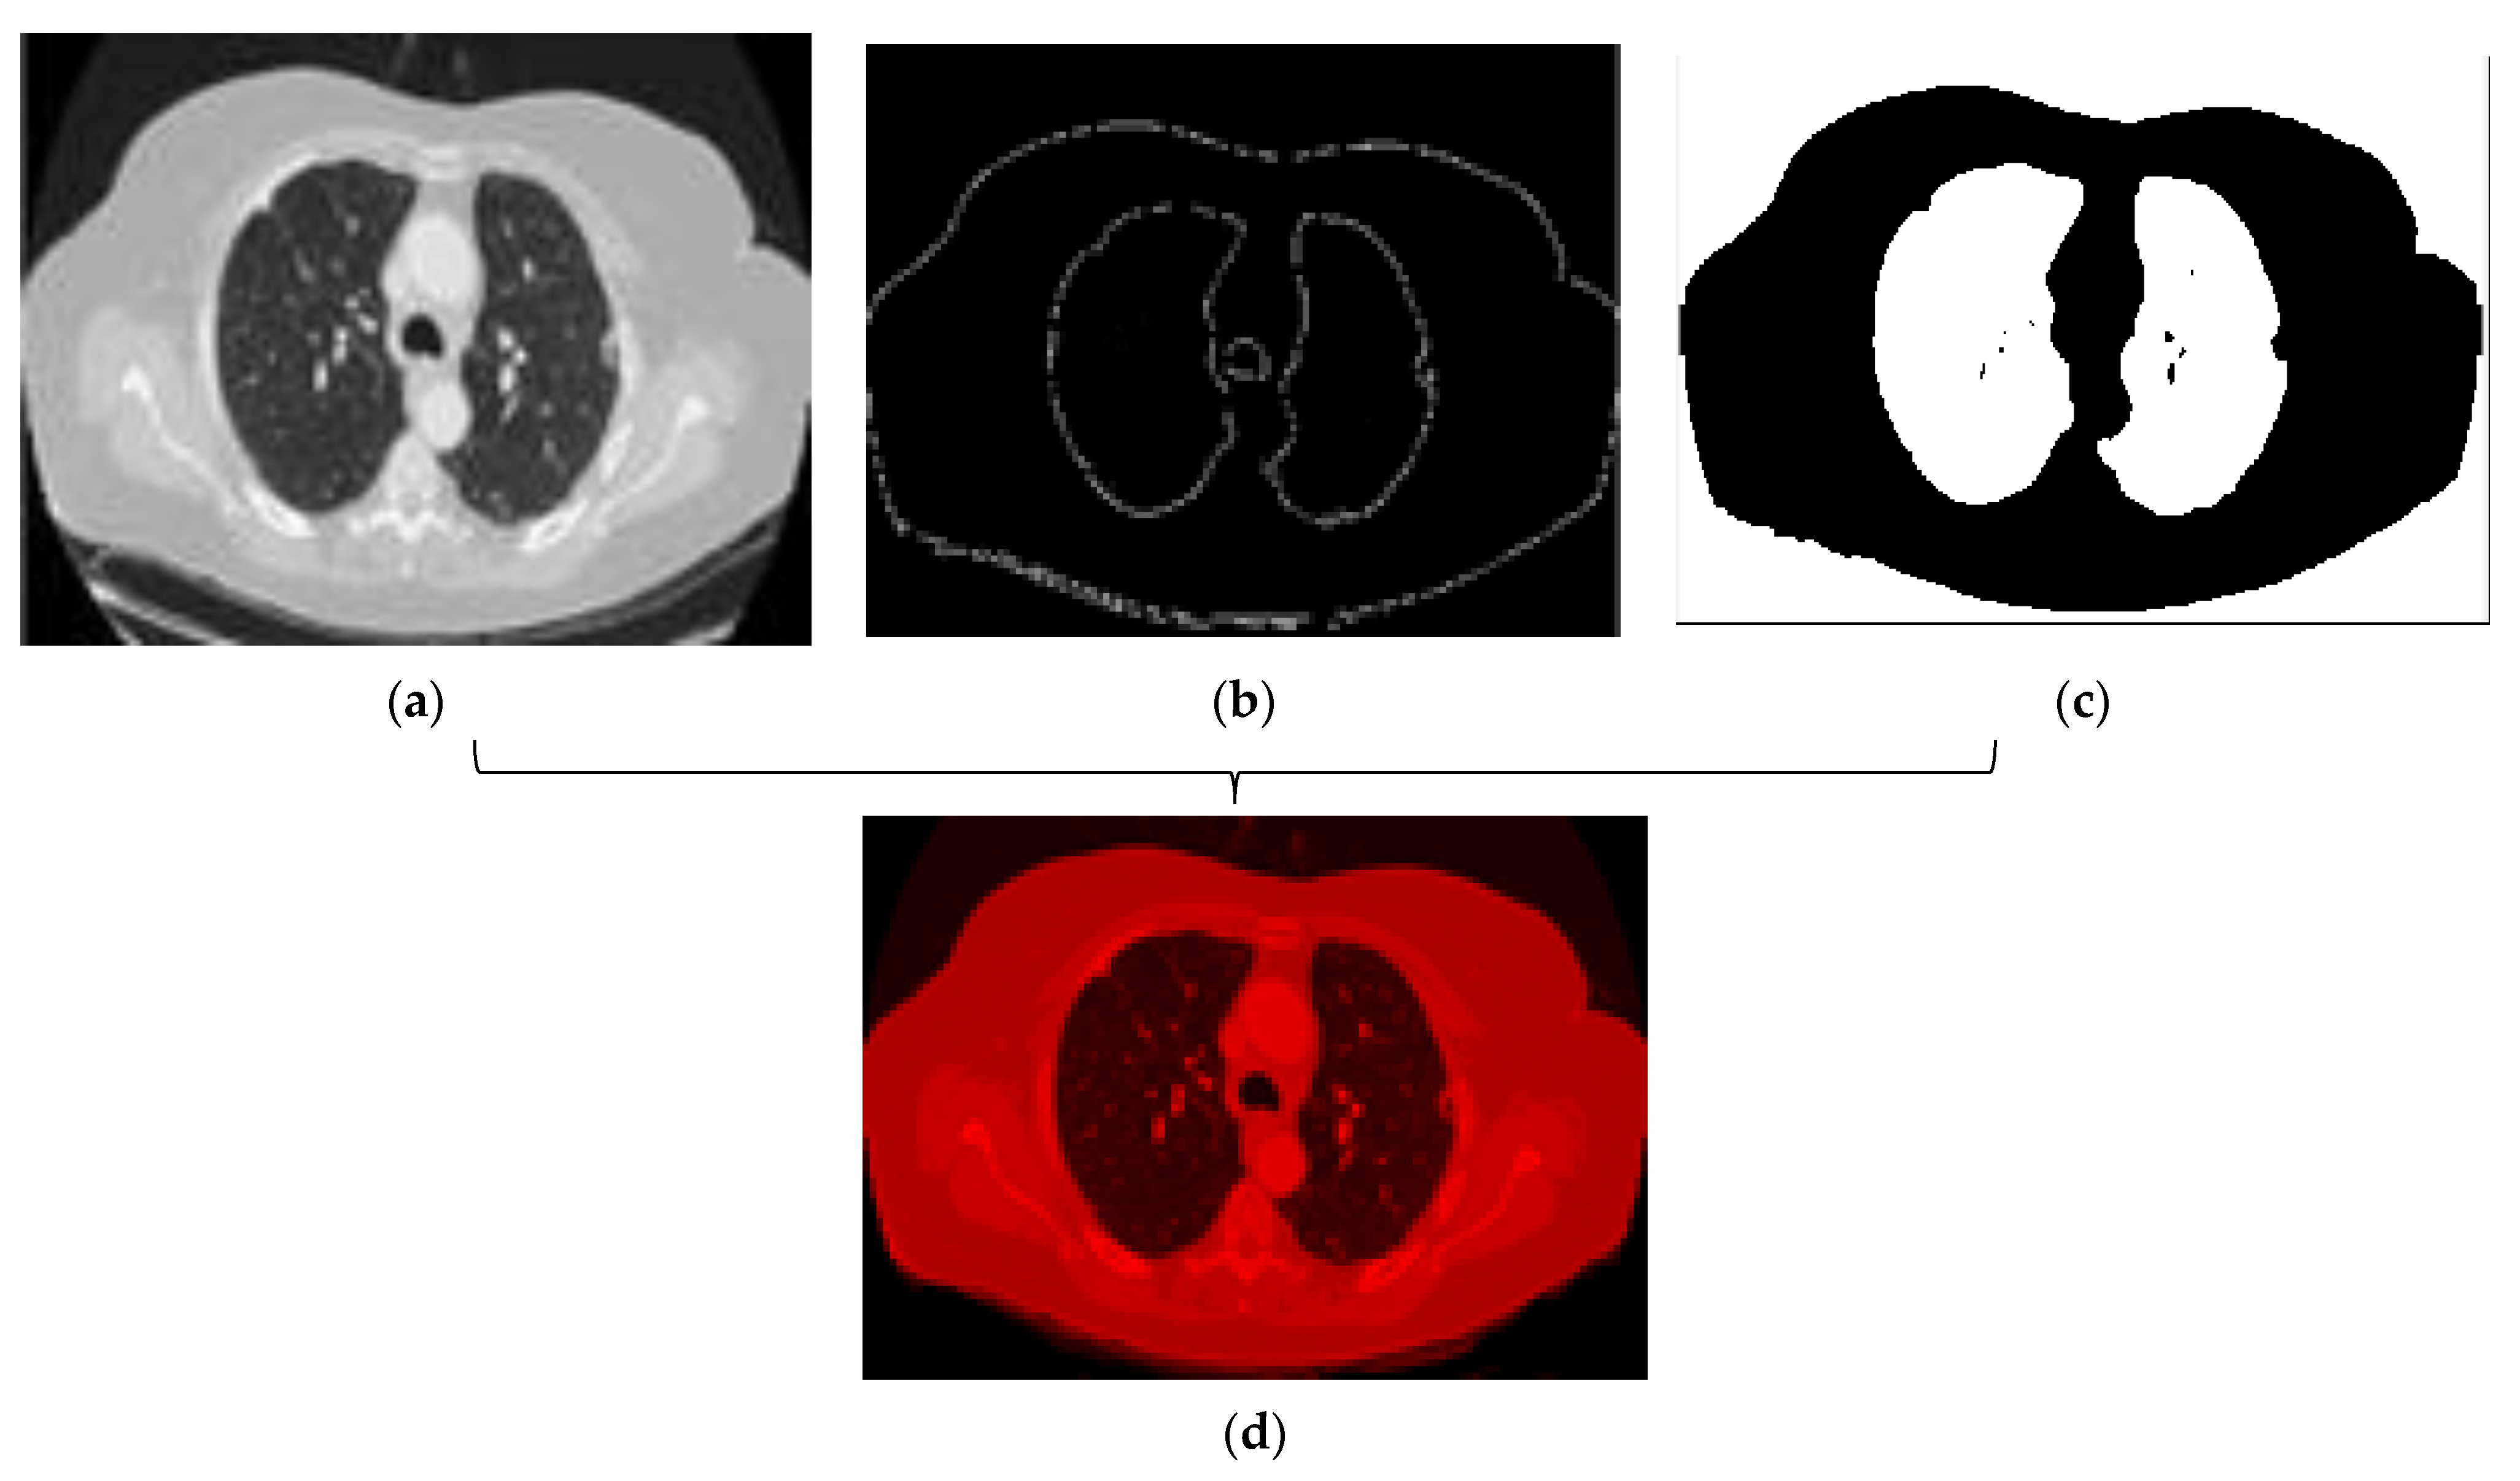

- Edge detection: As already stated, the edge detection filter determines the vertices of an object and the boundaries between objects and the background in the image. This process can also be used to improve the image and eliminate blur. An important advantage of the Canny technique is that it tries to remove the noise of an image before edge extraction and then applies the tendency to find the edges and the critical value of the threshold. Motivated by the advantages expressed so far, we also applied the Canny method to detect the edges in the source images. Figure 10 shows the result of the edge detection process.